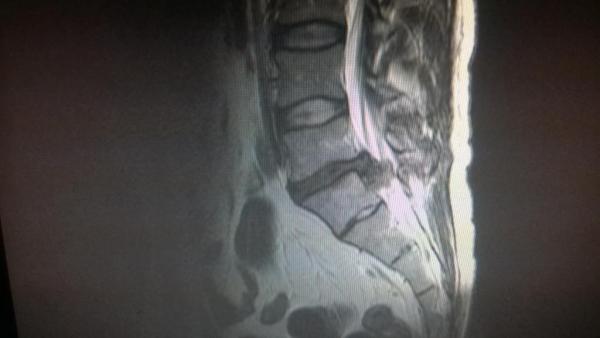

Ogólnie strasznie przerazające są te zdjęcia dla laika  :blink:

Jak się przegląda tą plyte i zdjęcia, ktore sie na siebie nakładają... najgorsze jest to oczekiwanie na interpretacje..

profilowo ;)

Wkleiłeś swój rezonans czy tam TK to ja wkleje swoje na szczęście z przed 5 czy 6 lat

Kto rozpozna co było problemem  :D

Wypadnięcie dysku? ;)

He he - ludzie z branży nie biorą udziału w konkursie - zapomniałem dodać  :lol:

Ale tak to prawda - bolało oj bolało  -_-  :(